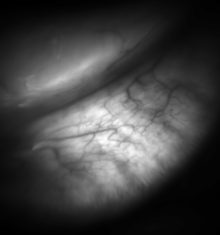

![Meibomian glands in the lower eyelid imaged under amber light to show vasculature support and the gland structure [epiCam].](../I/m/Meibomian-glands.png)

Meibomian gland dysfunction is more often seen in women and is regarded as the main cause of dry eye disease.[7][8] Factors that contribute to meibomian gland dysfunction can include things such as a person's age and/or hormones.[9] Treatment can include warm compresses or expression of the gland by a professional. In some cases antibiotics or steroids are prescribed.